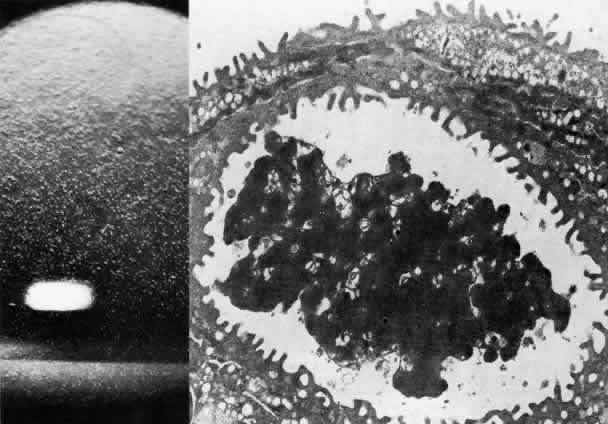

dystrophy and dominant hereditary endothelial dystrophy. Am J Ophthalmol 85:606, 1978 175. Kenyon KR, Maumenee AE: The histological and ultrastructural pathology of congenital hereditary

corneal dystrophy: A case report. Invest Ophthalmol 7:475, 1968 176. Pearce WG, Tripathi RC, Morgan G: Congenital endothelial lial corneal dystrophy: Clinical, pathological and

genetic study. Br J Ophthalmol 53:577, 1969 177. Kanai A, Kaufman HE: Further electron microscopic study of the hereditary corneal edema. Invest Ophthalmol 10:545, 1971 178. Kanai A, Waltman S, Polack FM et al: Electron microscopic study of hereditary corneal edema. Invest Ophthalmol 10:89, 1971 179. Antine B: Histology of congenital hereditary corneal dystrophy. Am J Ophthalmol 69:964, 1970 180. Kenyon KR, Maumenee AE: Further studies of congenital hereditary endothelial dystrophy of the cornea. Am J Ophthalmol 76:419, 1973 181. Rodrigues MM, Waring GO, Laibson PR et al: Endothelial alterations in congenital corneal dystrophies. Am J Ophthalmol 80:678, 1975 182. Wolter JR: Secondary cornea guttata in interstitial keratopathy. Ophthalmologica 148:289, 1964 183. Laing RA, Sandstrom MM, Leibowitz HM: In vivo photomicrography of the corneal endothelium. Arch Ophthalmol 93: 143, 1975 184. Bourne WM, Kaufman HE: Specular microscopy of human corneal endothelium in vivo. Am J Ophthalmol 81:319, 1976 185. Cross HE, Maumenee AE, Cantolino SJ: Inheritance of Fuchs' endothelial dystrophy. Arch Ophthalmol 85:268, 1971 186. Krachmer JH, Purcell JJ Jr, Young CW et al: Corneal endothelial dystrophy: A study of 64 families. Arch Ophthalmol 96:2036, 1978 187. Polack FM: The posterior corneal surface in Fuchs' dystrophy: Scanning electron microscope